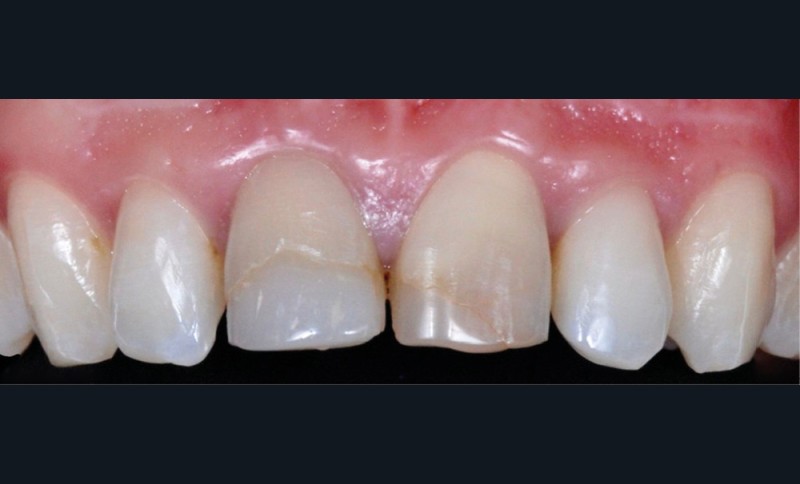

– le trauma, qui va donner une couleur plutôt rouge [4] (fig. 3) ;

– les soins conservateurs et endodontiques [5] (fig. 4 et 5).